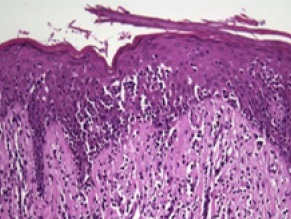

피부 생검을 통해 다음과 같은 소견이 나타나면 이 질환으로 진단한다.[15]

• 꼬인 윤곽(뇌회형 핵)을 가진 암세포가 존재한다.

• 반점 및 판 단계에서는 암세포가 표피(피부의 가장 얕은 층)에서 관찰된다. [16] 이를 표피친화성이라고 한다.

• '''파우트리에 미세농양'''은 표피에 배열된 4개 이상의 비정형 림프구의 집합이다. 이는 균상식육종의 특징이지만, 일반적으로 나타나지는 않는다.

• 종양 단계에서 암세포는 진피(피부의 더 깊은 층)로 이동한다.[16]

• 대세포 변형은 병변 내에서 동일한 림프구가 비대증을 보이는 경우를 말하며, 변형된 세포에서 CD30 수용체가 존재하면 생존율 향상과 관련이 있다.[17]

피부 T세포 림프종에서 파우트리에 미세농양의 조직병리학적 소견